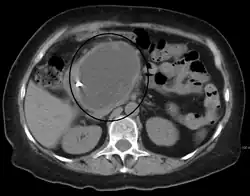

| A pancreatic pseudocyst as seen on CT | |

A pancreatic pseudocyst is a circumscribed collection of fluid rich in pancreatic enzymes, blood, and non-necrotic tissue, typically located in the lesser sac of the abdomen. Pancreatic pseudocysts are usually complications of pancreatitis,[5] although in children they frequently occur following abdominal trauma. Pancreatic pseudocysts account for approximately 75% of all pancreatic masses.[6]